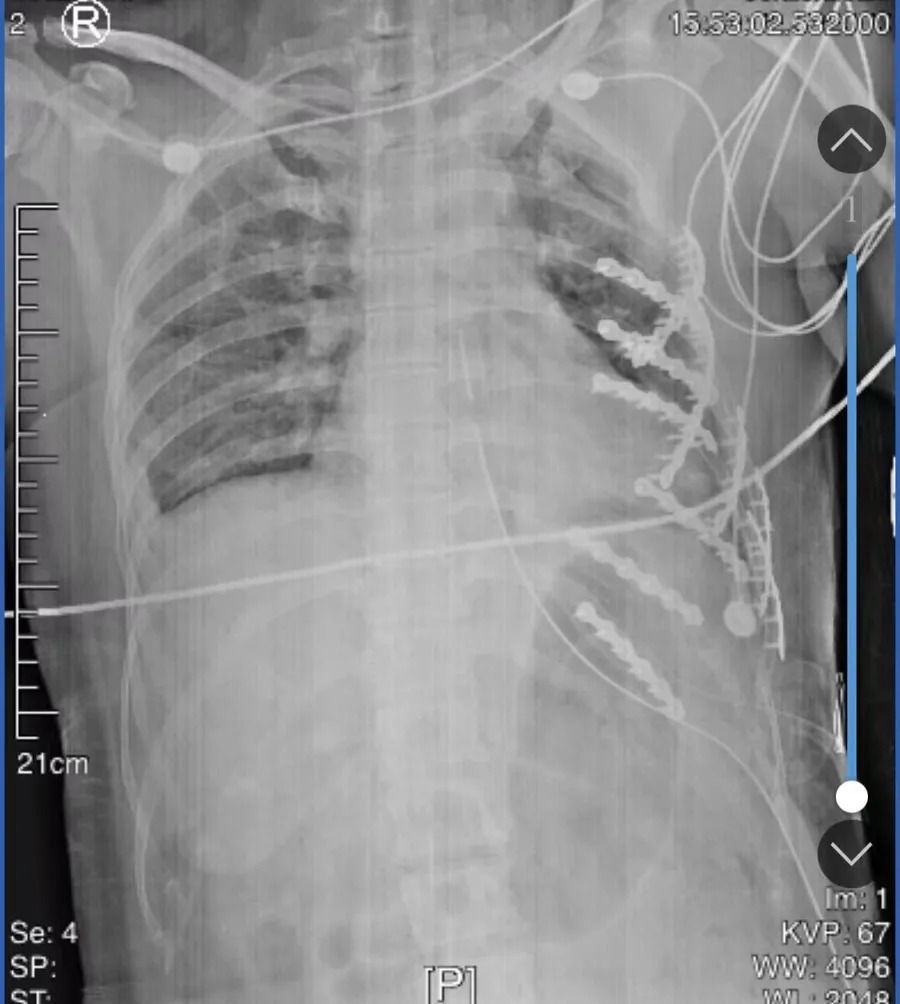

术前影像检查结果显示,患者胸部因遭受剧烈挤压,导致胸壁严重软化塌陷,胸腔有大量积液。张己为医生介绍:“人体胸腔共有24根肋骨,患者断了20根,尤其左侧伤情最为严重——第1至第12根肋骨全部骨折,部分肋骨呈多处断裂,错位明显,骨折碎片已刺破壁层胸膜,并深深扎入左肺上下叶,左侧和右侧肋骨共有40多处断裂。”

术中发现,患者因肋骨骨折刺破胸膜,胸腔内积血达500多毫升。术中实施输血、止血、修补缝合等抢救措施,患者生命体征逐渐趋于稳定。随后,手术医生在胸腔镜辅助下股市配资交易论坛,精准完成骨折复位,并采用直型钢板及螺钉对多处骨折断端进行了牢固的内固定,完成胸廓重建。经过胸外科、骨科、麻醉科及手术室护理团队五个多小时的紧密协作与奋力救治,手术圆满成功,患者转危为安。